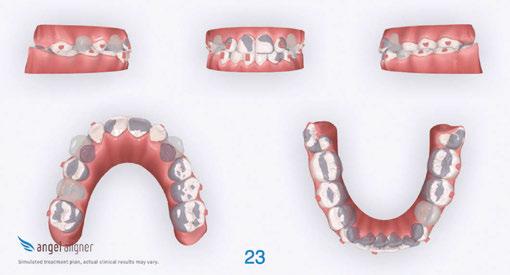

Treatment progression

The primary phase of treatment had a total of 20 sets of aligners, and we saw the patient for three appointments (Figure 4). His compliance with aligner wear and tracking was excellent. We were pleasantly surprised by how well he adapted to both the aligners and attachments, especially given his severe oral sensitivities.

Figure 2A (top): Initial set-up in iOrtho. Figure 2B (bottom): Superimposition view of the initial set-up in iOrtho

Figure 4: JA refinement records 4 months into treatment (10.11 years old). Upper and lower expanded. Refinement goals were to complete alignment and space consolidation and exaggerate U2 mesial root tip

Figure 5: JA final photos — 10 months total treatment time. Upper and lower arches expanded and aligned, anterior spacing consolidated, midlines centered, and U2 mesial root tip exaggerated